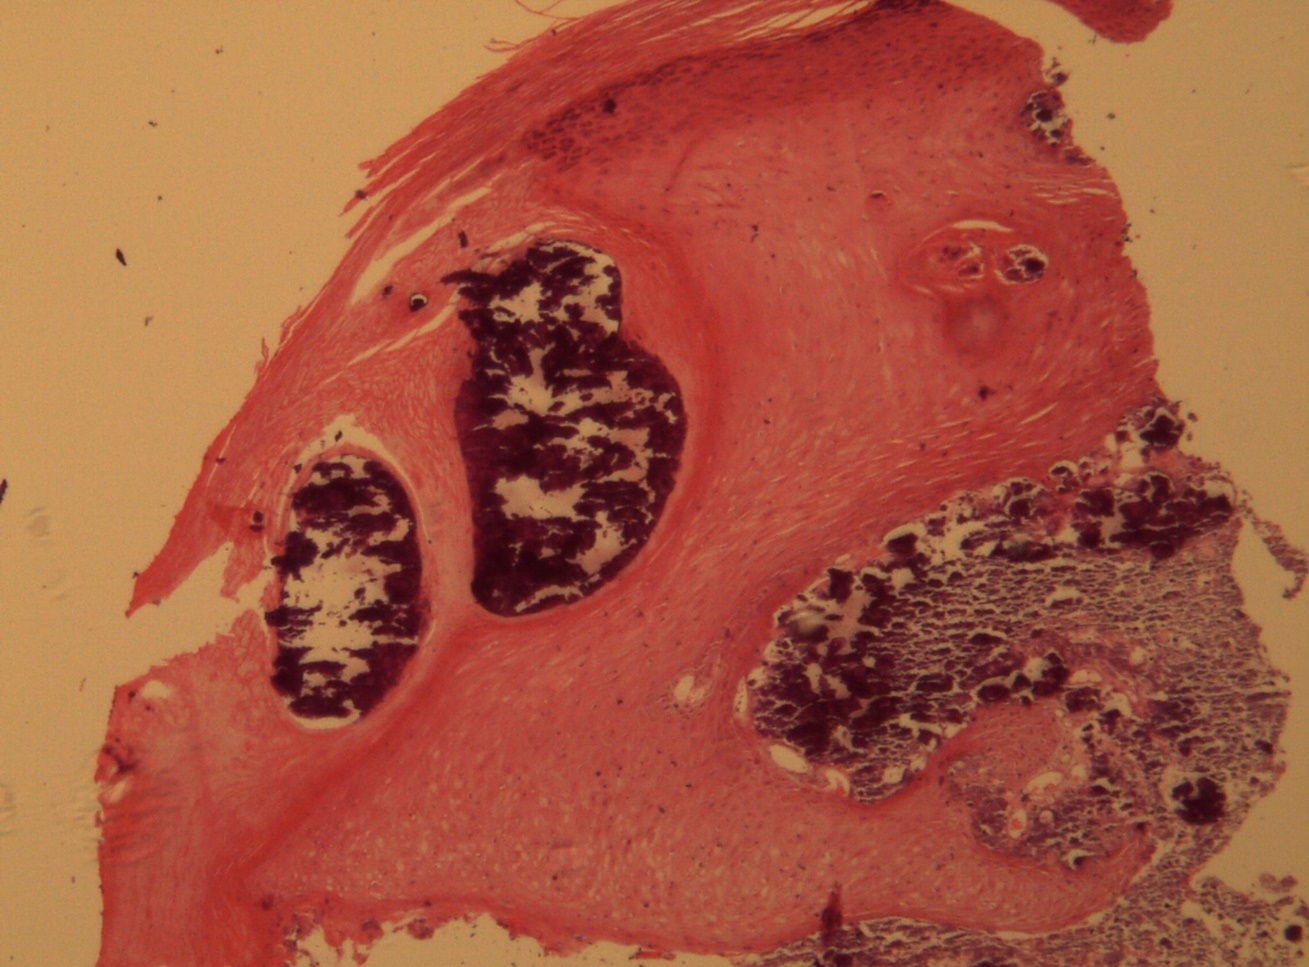

A 9-year-old male patient who was treated in the dermatology service for a progressively growing keratotic nummular dermal lesion on the right knee. With the clinical judgment of viral wart, the lesion was removed. In the Pathology Service, a nummular keratotic lesion of 0.5 cm in maximum dimensions was received, which crackled when cut. Figure 1, Figure 2, Figure 3, Figure 4, Figure 5

Figure 3.Relationship of calcium foci in the papillary dermis with the overlying epidermal hyperplasia. HE. 200x.